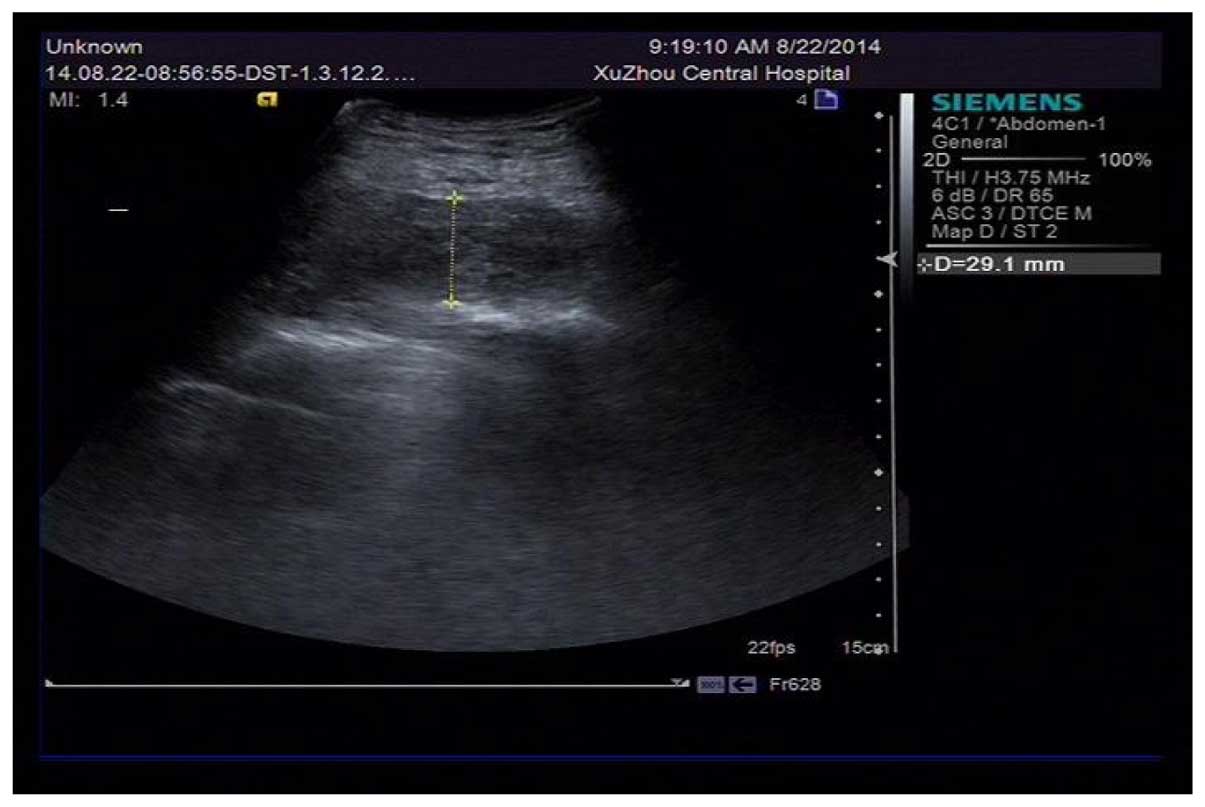

Spontaneous hematoma in the setting of dual anti-platelet therapy with ticagrelor: A case report

A 69-year-old male patient was admitted to hospital because a lump was discovered, accompanied with pain lasting 5 h under his right scapula. Two months earlier, he had undergone a double-stent insertion operation due to lesions on the end of the left main coronary artery, the opening of left circumflex artery, and the opening of the anterior descending branch. After the operation, he was administered with dual anti‑platelet therapy (DAPT) with aspirin and ticagrelor and was diagnosed with hematoma under his right scapula through ultrasonic inspection. It was established that no other factor, except DAPT, was responsible for his spontaneous hematoma.

Figure 2